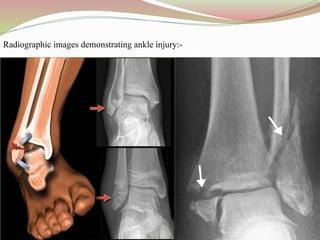

Radiographic images demonstrating ankle injury:-

3. ANKLE INJURY: Is the injury that happens when one or more bones in the ankle

joint break.

 CAUSES: This can be caused by:-